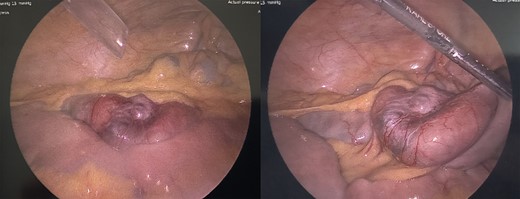

An urgent diagnostic laparoscopy was performed during which a hyperchromic, obstructing mass in the ileum was found (Fig. 3). No additional intraabdominal lesions were visualized. The portion of small bowel was extracorporealized, resected, and a primary stapled anastomosis was performed. The specimen revealed malignant melanoma (Fig. 4), positive for Melan A and S100 immunostains (Fig. 5) and for BRAF V600K mutation. A PET scan was finally performed 3 days postsurgery in which increased uptake was seen in the left lateral abdomen and in multiple bilateral pulmonary nodules (Fig. 6). He was discharged to a rehabilitation center.

Resected portion of jejunum containing an obstructing melanoma metastasis.